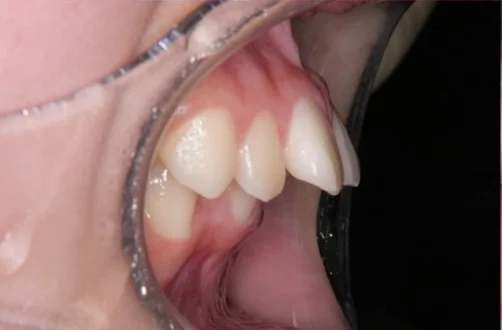

治療前

| 相談内容(主訴) | 出っ歯が気になる |

|---|---|

| 診断結果/行った治療内容 | 上顎前突/インビザライン矯正 |

| 治療期間/回数 | 1.5年/18回 |

| 治療費用 | 80万円 |

| 治療のリスク/副作用 | 歯の移動に伴い歯肉退縮を起こすことがあります/顎関節に症状が出ることがあります |